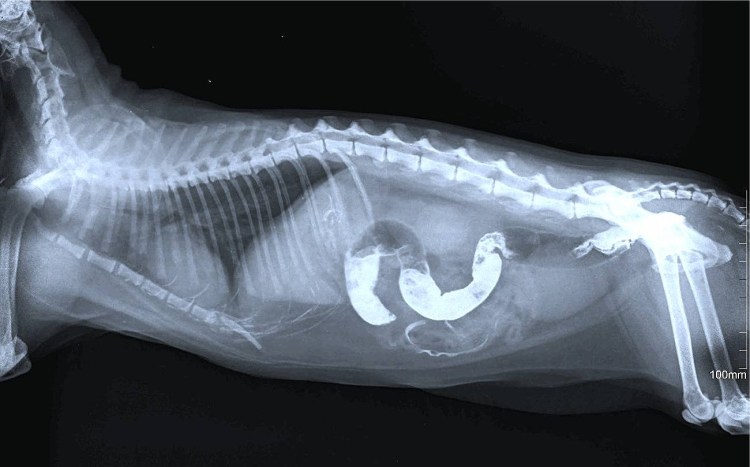

![Кишечная непроходимость на рентгене у собаки]()

Кишечная непроходимость на рентгене у собаки